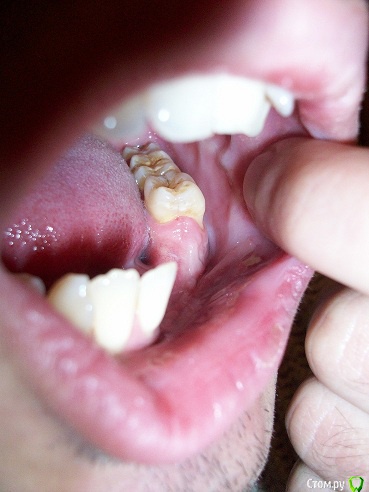

mikheil.osipov Опубликовано 16 декабря, 2015 Поделиться Опубликовано 16 декабря, 2015 Доброго времени сутокЧетыре месяца назад, 2-го августа, я попал в аварию и получил перелом нижней и верхней челюсти. На нижней челюсти был односторонний открытый перелом, а также перелом альвеолярного отростка с 1-го по 5-й зубы. Также был поврежден нерв, потеря чувствительности левой части губы и подбородка. Мне сделали операцию – на нижней челюсти провели остеосинтез титановой пластиной, альвеолярный отросток закрепили шинами, а на верхнюю наложили шов проволокой. По какой то причине нижняя челюсть пложо заживала, альвеолярная кость местами была оголена и даже был виден край ушка пластины, врач назначил солкосериловую мазь, один раз сделал пластику, но кость опять оголилась. Врачь сказал, что начался некроз (странно, но температуры и гноя не было) и 20 октября удалил отломонный отросток. После удаления прошло почти два месяца, 4 месяца после перелома, 6 декабря я снял томографию и вроде бы заживление идет нормально, но теперь у меня проблемы с дальнейшей имплантацией из-за недостатка костной ткани. Мне 25 лет и хотелось бы востановить утраченные зубы с учетом качества и долговечности. Возможно ли установить импланты и нужно ли для этого наращивание кости? Прошу подскажите какой будет оптимальный метод протезирования в моем случае? Ниже я выкладываю старую и новую 3D томографии и фото. Томография и фото до удаления:Ссылка на томографию: https://drive.google.com/open?id=0B4pglooYIfg_TXJSUXVEQ2p0b2c Последняя томография и фото:Ссылка на томографию: https://drive.google.com/open?id=0B4pglooYIfg_aVhLSHRobkZHdzA Заранее спасибо! Ссылка на комментарий

mikheil.osipov Опубликовано 17 декабря, 2015 Автор Поделиться Опубликовано 17 декабря, 2015 Так было до удаления: Вот панорама и снимки: Ссылка на КТ https://drive.google.com/open?id=0B4pglooYIfg_aVhLSHRobkZHdzA Я был на консультации и мне сказали что нужна пластика искуственной костью и каркасом. Также сказали, что верхние винты могут помешать при имплантации и их надо будет снять. Врачь сказал, что ситуация сложная, также недостаток мягких тканей создает проблемы. Возможно ли обойтись без каркаса? Ведь его установка и у даление дополнительная травма и есть риск осложнений. Возможно ли установить импланты более простым методом? Ссылка на комментарий